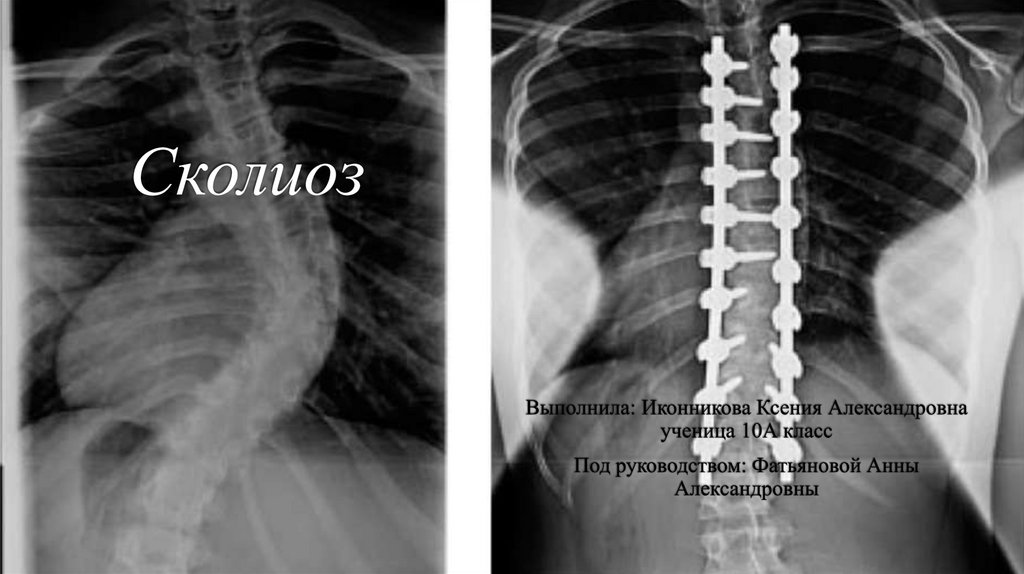

Моя жизнь и сколиоз

10.

ДО:

ПОСЛЕ:

05.11.2025